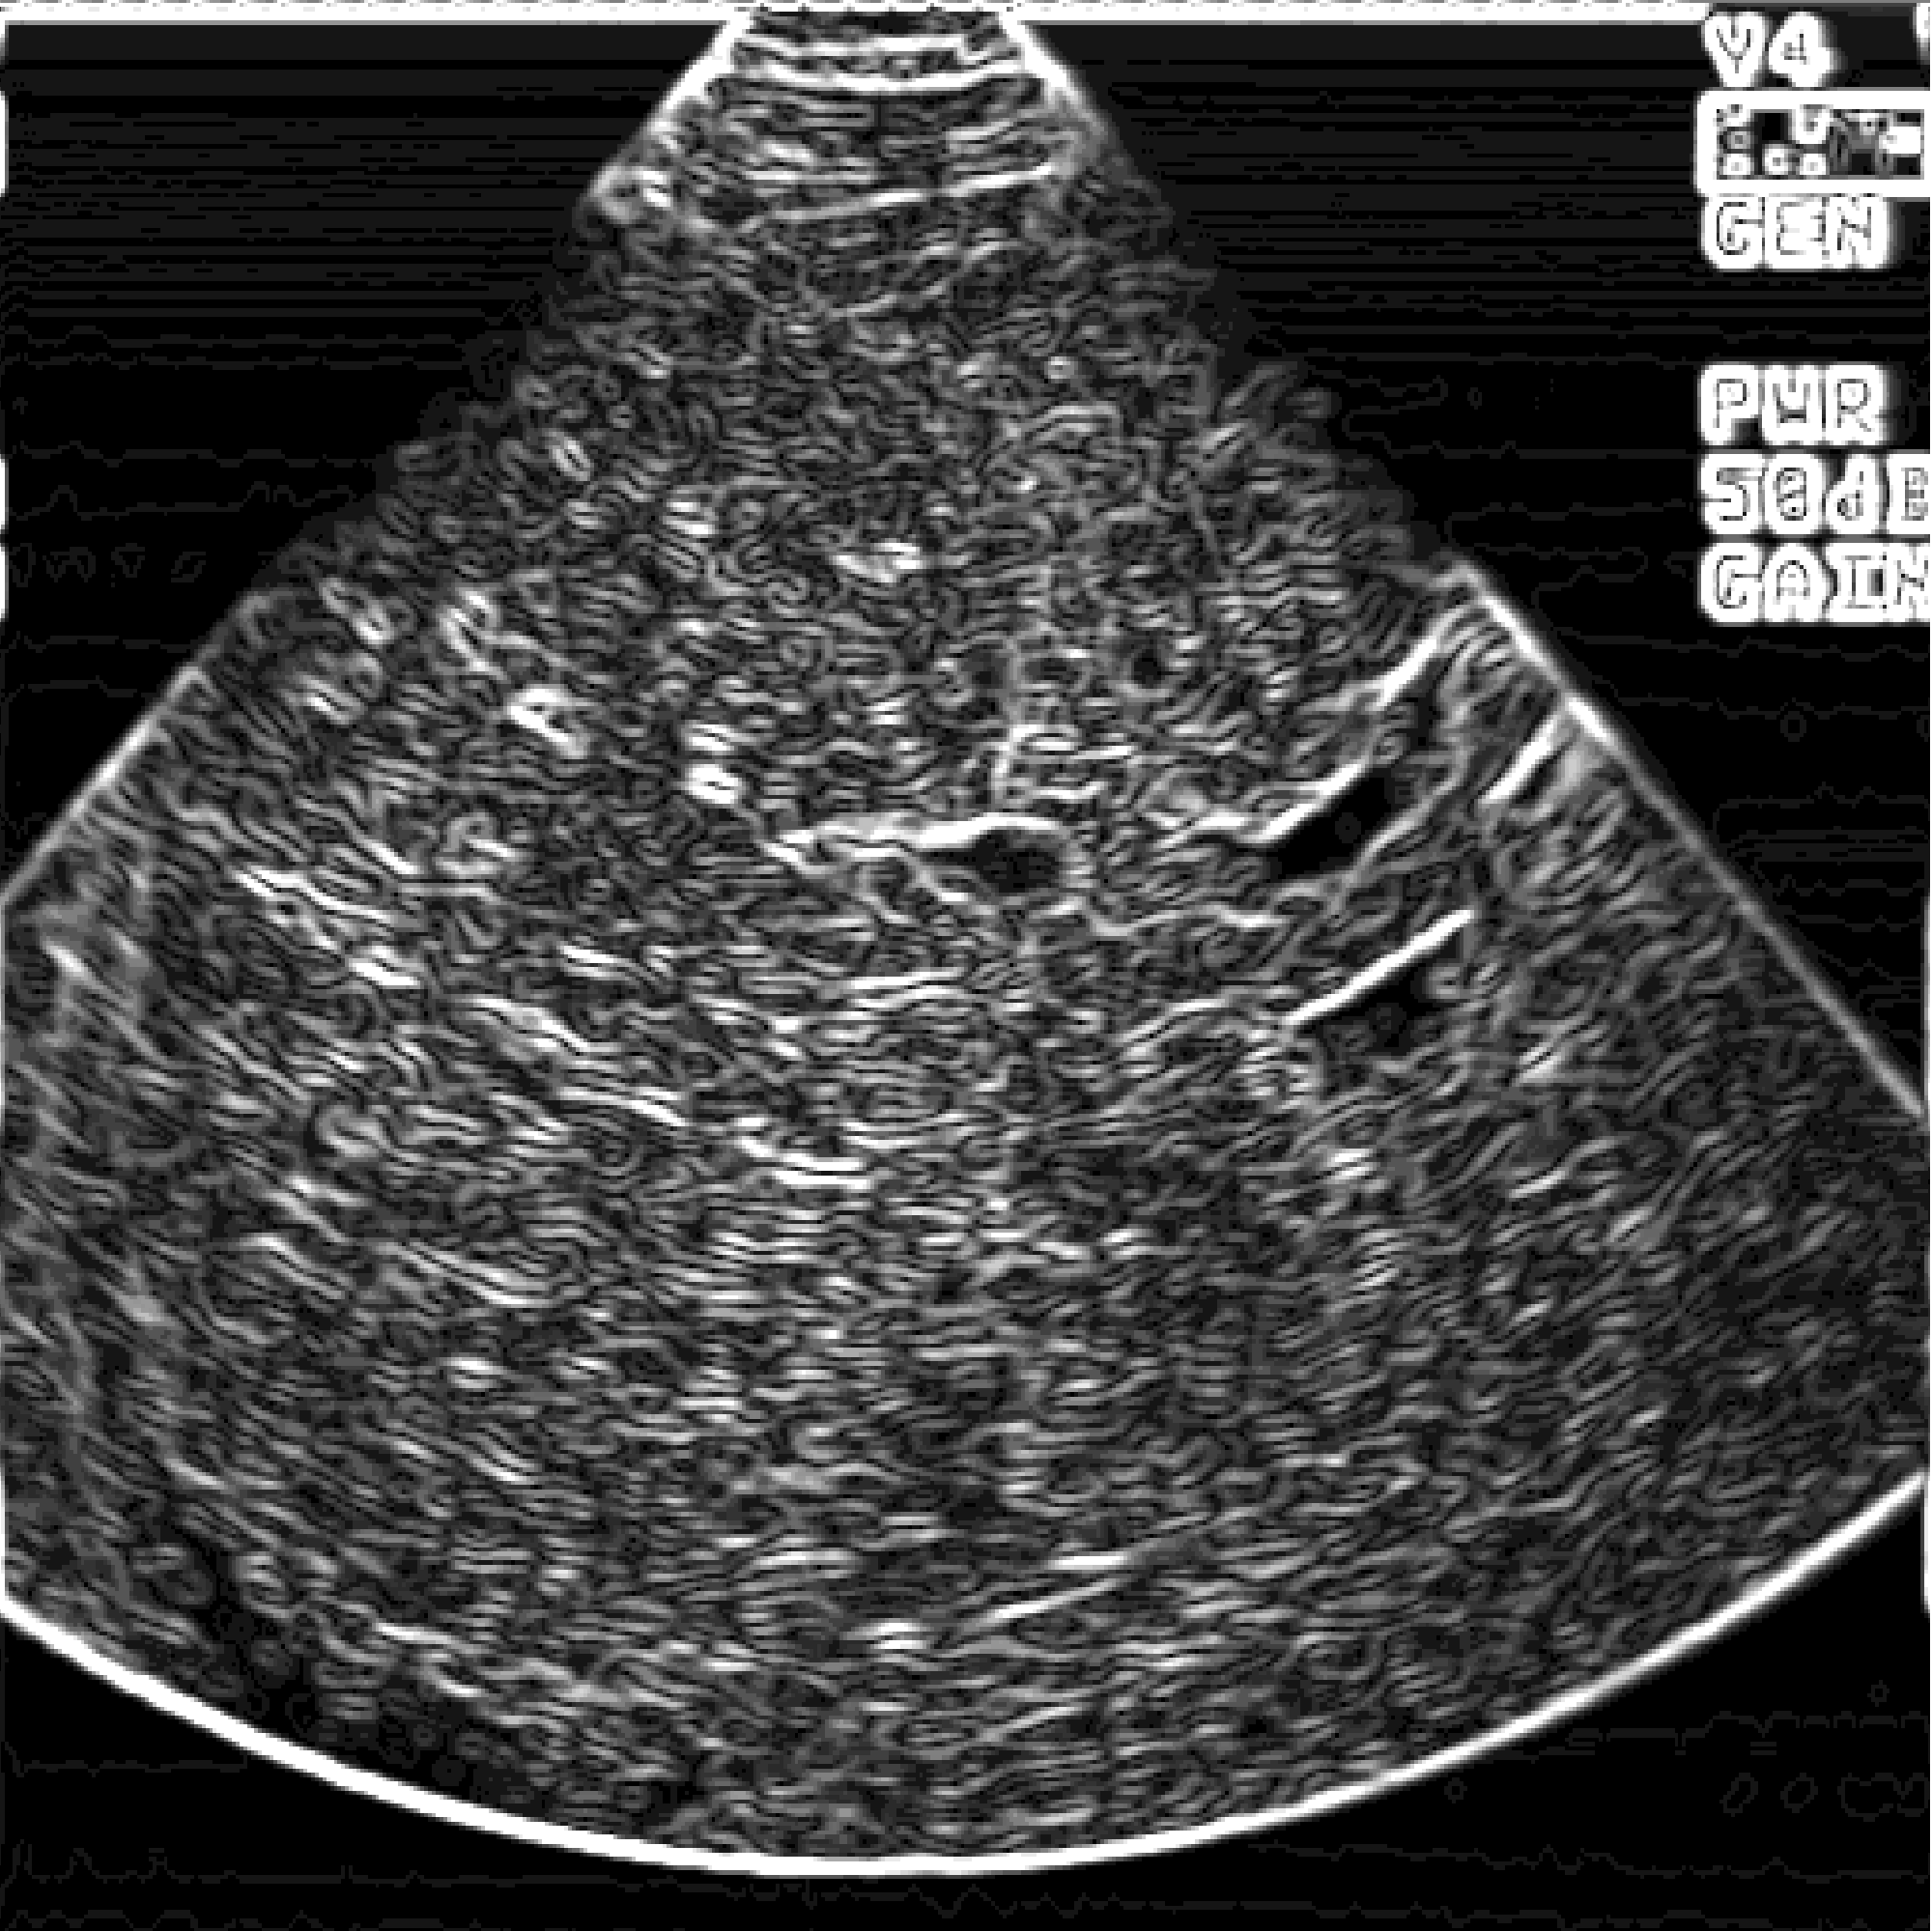

Для решения данных проблем разработана следующая схема передачи данных из ультразвуковой медицинской диагностической установки в персональный компьютер. (плакат 1) Я осуществлял подключение ультразвуковой диагностической установки ALOCA SSD 650. Она осуществляет срез информации органов исследуемого пациента на глубину до 30 см. от места контакта с телом пациента и работает на частоте от 2 до 7,5 мГц. И выводит информацию на экран с разрешением 640 * 480 с 64 уровнями градации серого. Полученная информация преобразуется в стандартный видеосигнал, который может быть снят с специализированных выходов. Захват и обработку информации из ультразвуковой медицинской установки осуществляется устройством, называющимся frame grabber. Оно позволяет в «реальном времени» преобразовать видеосигнал в цифровое изображение и сохранить его в персональном компьютере. К frame grabber’у предъявляется ряд характерных требований. Это должно быть устройство, позволяющее длительную оцифровку видеосигнала в реальном времени, обладать высокоскоростной «шиной», для быстрой передачи полученной информации в персональной компьютер. В нем должна быть предусмотрена возможность настройки яркости и контрастности для первоначальной настройки при подключении к медицинской диагностической установке и оно должно быть совместимо со всеми основными современными операционными системами. Всем этим требованиям удовлетворяет frame grabber HI*DEF PLUS фирмы IMAGRAPH. Данный frame grabber позволяет получать 256 уровней градации серого, что позволяет иметь запас по разрешению изображения для ультразвуковых медицинских установок более высокого класса и получать изображения, над которыми можно производить определенные операции. Кроме того, это сравнительно недорогое устройство, в своем классе, что является преимуществом, т.к. наши медицинские учреждения финансируются не достаточно. Frame grabber передает информацию в передает информацию в персональный компьютер первичного пользователя. Оптимальной конфигурацией персонального компьютера первичного пользователя является P2 – 400, 128, 4.3 + 18 SCSI, 8 V I740. Данная конфигурация предоставляет возможность осуществлять захват изображения из ультразвуковой медицинской диагностической установки, поддерживать режим телеконференций, осуществлять передачу получаемого сигнала по сети в реальном времени и обрабатывать получаемую информацию. Но т.к. парк персональных компьютеров в медицинских учреждениях России, на данное время, состоит из персональных компьютеров устаревших моделей, то в этом случае можно использовать лишь основные функции - захват и обработку изображений. Это можно осуществлять на персональных компьютерах класса DX4 – 100 с 16 мБ оперативной памяти, размером жесткого диска 800 мБ и сетевой картой NE2000 или совместимой. Персональный компьютер первичного пользователя позволяет передавать полученную информацию по компьютерной сети. Вопросы передачи информации по компьютерной сети подробно рассматриваются в дипломном проекте Еремеева Артема, который также выполнял дипломную работу в рамках проекта «телемедицина». К персональному компьютеру вторичного пользователя предъявляются те же требования, что и к персональному компьютеру первичного пользователя, за исключением того, что у в нем не устанавливается frame grabber для захвата изображения с ультразвуковой медицинской диагностической установки. В результате захвата изображения получается файл в котором необходимо отобразить не только информацию собственно о картинке, но и дополнительную. Для этого был разработан формат файла плакат 2 , который содержит в себе следующие поля:

Информационное поле данного файла на прямую связано с характеристиками ультразвуковой медицинской диагностической установки, frame grabber’а и персональным компьютером. В рамках данной работы, в результате взаимодействия с медицинским персоналом, возникла необходимость преобразования изображений для выделения областей, контуров этих областей, границ образований. Для этого мною были внедрены ряд фильтров. Это сглаживающий фильтр, медианный сглаживающий фильтр, контурный фильтр и полутоновой фильтр. Результаты воздействия данных фильтров на изображение можно наблюдать плакат 3. По результатам консультирования с врачами, было выявлено, что их применение дает наиболее хороший эффект при последовательном воздействии на изображение нескольких фильтров. Это можно наблюдать на плакате 4. Это было апробировано специалистами и было выявлено, что результаты воздействия этих фильтров на изображение несут в себе высокую практическую ценность. В данной дипломной работе было: